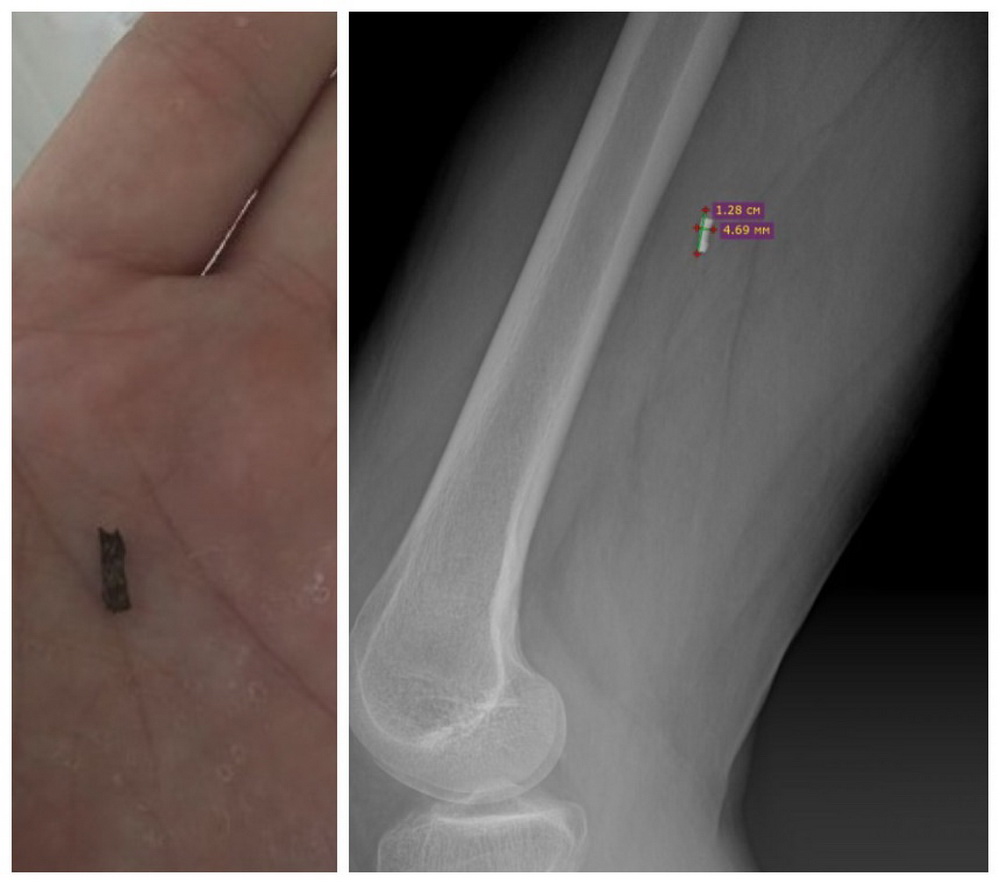

«Максимально освободили нерв от рубцов и спаек, восстановили анатомическую целостность структур и физиологическое расположение нерва. В области малоберцового нерва удалено само инородное тело размером 1,28 см × 4,69 мм», — цитирует пресс-служба ННИИТО врача-нейрохирурга Ивана Копылова.

Фото: пресс-служба Новосибирского НИИТО имени Я. Л. Цивьяна